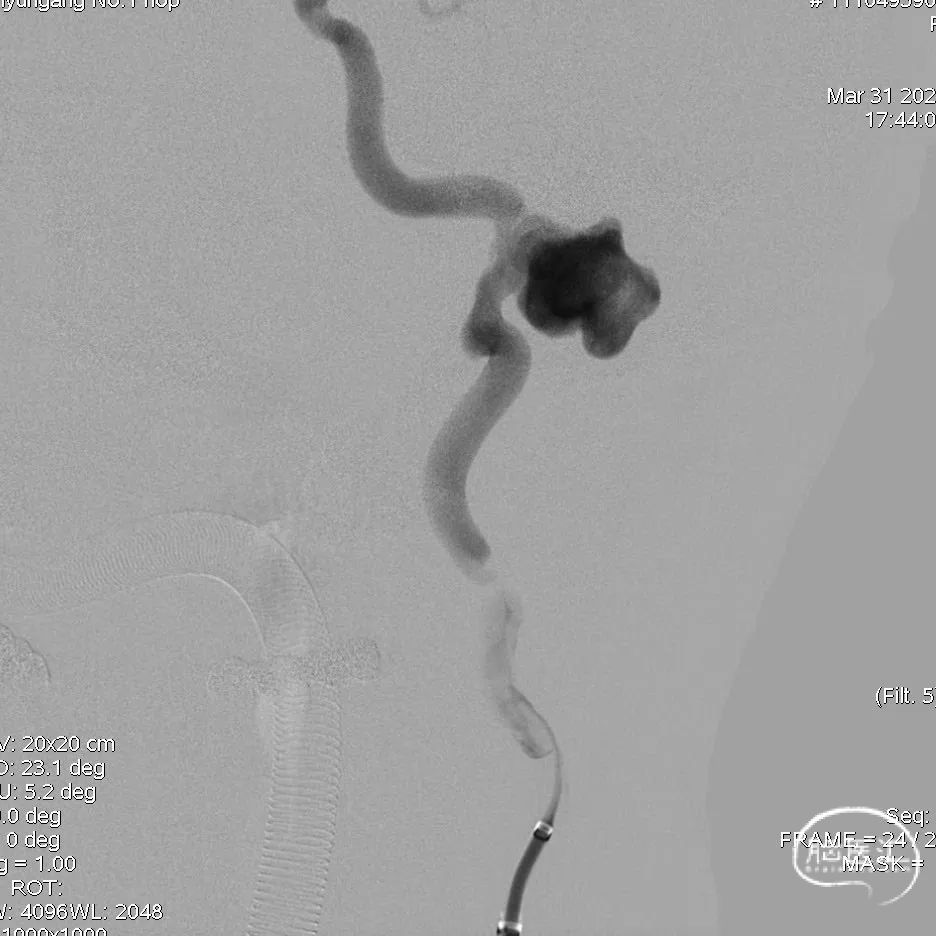

DSA提示左侧颈内动脉岩段 巨大、多发、夹层、假性 动脉瘤。

DSA选取工作角度

测量载瘤动脉远端直径4.5±0.2mm,近端直径6.0±0.3mm,预计覆盖长度40mm+。